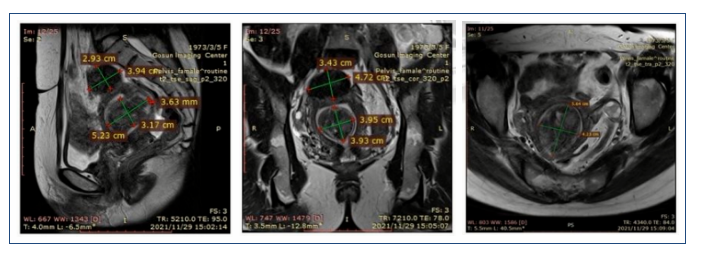

患者49岁,G4P1。

子宫肌瘤病史7年,月经过多1年。血红蛋白量下降至85g/L。

影像学表现: